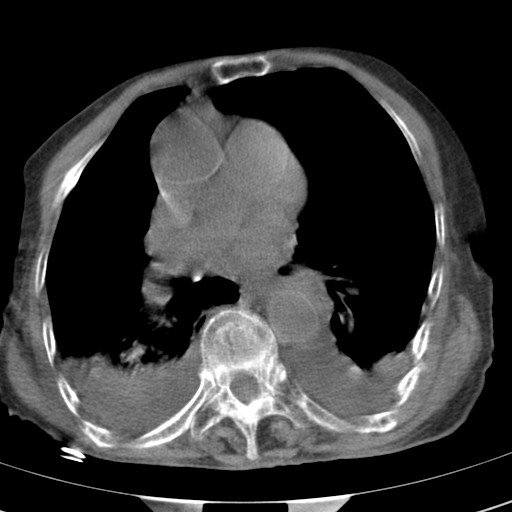

标题: CT21467:女,93岁,摔伤后检查。

女,93岁,摔伤后检查。

右肺炎症,心功能不全伴双侧胸腔积液,右下肺膨胀不全,食管裂孔疝,冠脉钙化,心包少量积液,左侧肋骨骨折,请上传骨窗.

右侧锁骨\\肩胛骨骨折、右侧湿肺,心功能不全伴双侧胸腔积液,右下肺膨胀不全,左膈破裂或食管裂孔疝,冠脉钙化,心包少量积液,请上传骨窗.

右肺炎症,心功能不全伴双侧胸腔积液,右下肺膨胀不全,食管裂孔疝,冠脉钙化,心包少量积液,左侧肋骨骨折,右肩甲骨粉碎性骨折。93岁,高寿哇!

右肺炎症,心功能不全伴双侧胸腔积液,右下肺膨胀不全,食管裂孔疝,冠脉钙化,心包少量积液,左侧肋骨骨折,右肩甲骨粉碎性骨折。